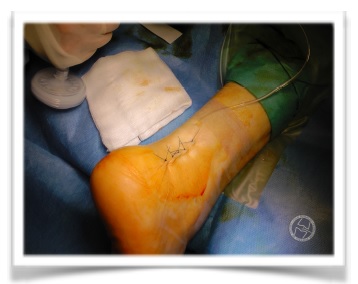

Primer paso quirúrgico:

Incisión para aquilea lateral y profundización hasta ladisección del os trigonum; resección del mismo, que

no pudo realizarse completamente sino por fragmentos.

Segundo paso: localización del astrágalo y perforación del mismo para realizar infiltración intraósea de PRP (plasma autólogo rico en plaquetas.

Tercer paso: Infiltración de PRP en el tendón flexor largo del hallux y en la articulación subastragalina posterior, en la tibio-peroneo-astragalina y en estructuras profundas de la región posterior del tobillo derecho.

Cierre quirúrgico:

Cierre del subcutáneo y de la piel mas colocación de un sistema de drenaje Redón de aspiración, que se mantuvo 24 horas.